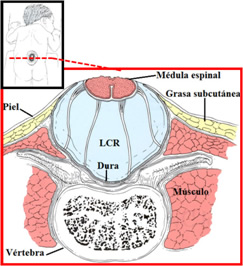

MIELOMENINGOCELE

También conocido como espina bífida abierta, el mielomeningocele es la forma de espina bífida más grave y la forma a la que las personas se refieren, por lo general, cuando usan el término espina bífida.

En el caso del mielomeningocele, el conducto vertebral del bebé queda abierto en varias vértebras de la parte inferior o media de la espalda. Debido a esta abertura, tanto las membranas que protegen la médula como la misma médula espinal sobresalen en el nacimiento y forman un saco en la espalda del bebé y son claramente visibles.

En algunos casos, la piel recubre el saco. Sin embargo, por lo general, los tejidos y los nervios quedan expuestos, lo que aumenta las probabilidades de que el bebé tenga infecciones que pongan en riesgo su vida.

La médula espinal puede estar dañada o no bien desarrollada. Su localización más frecuente es la región lumbar o lumbosacra.

Hidrocefalia

La acumulación del líquido cefaloraquídeo puede producir presión e inflamación en el cerebro.

En el 80 por ciento de las personas afectadas por espina bífida, la hidrocefalia sólo se puede tratar insertando un tubo de drenaje llamado “derivación de líquido cefalorraquídeo”.

No existen medicamentos que puedan tratar la hidrocefalia con eficacia. La derivación se coloca debajo de la piel desde la cabeza (ventrículos) hasta la cavidad abdominal, donde el líquido cefalorraquídeo es rápidamente reabsorbido por el cuerpo.